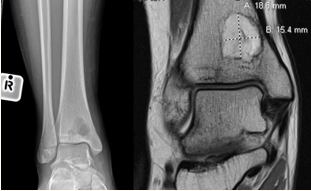

Radiographs

Anteroposterior and lateral views of the affected limb. May be normal in early infection. At a later stage periosteal reaction can be seen. Can also identify air around soft tissue suggestive of an infection. Involucrum and sequestrum are features of chronic osteomyelitis.

Brodie abscess

A Brodie abscess consists of a region of suppuration and necrosis encapsulated by granulation tissue within a rim of sclerotic bone. Brodie abscess occurs in the setting of subacute osteomyelitis in the metaphysis of long bones, typically in patients < 25 years of age. It is usually of hematogenous origin but can also occur in the setting of trauma.

The most common pathogen is S. aureus. The most common site is the distal tibia; other sites include the femur, fibula, radius, and ulna.

Magnetic resonance imaging (MRI)

MRI is the imaging modality with greatest sensitivity for the diagnosis of osteomyelitis. After radiographic evaluation, MRI is generally considered the study of choice for further assessment. It is useful for obtaining images delineating the extent of cortical destruction characteristic of osteomyelitis, as well as to evaluate for presence of bone marrow abnormality, soft tissue inflammation (such as in the setting of cellulitis, myositis, and/or ulceration) and ischemia. MRI may demonstrate abnormal marrow edema as early as 1 to 5 days following onset of infection.